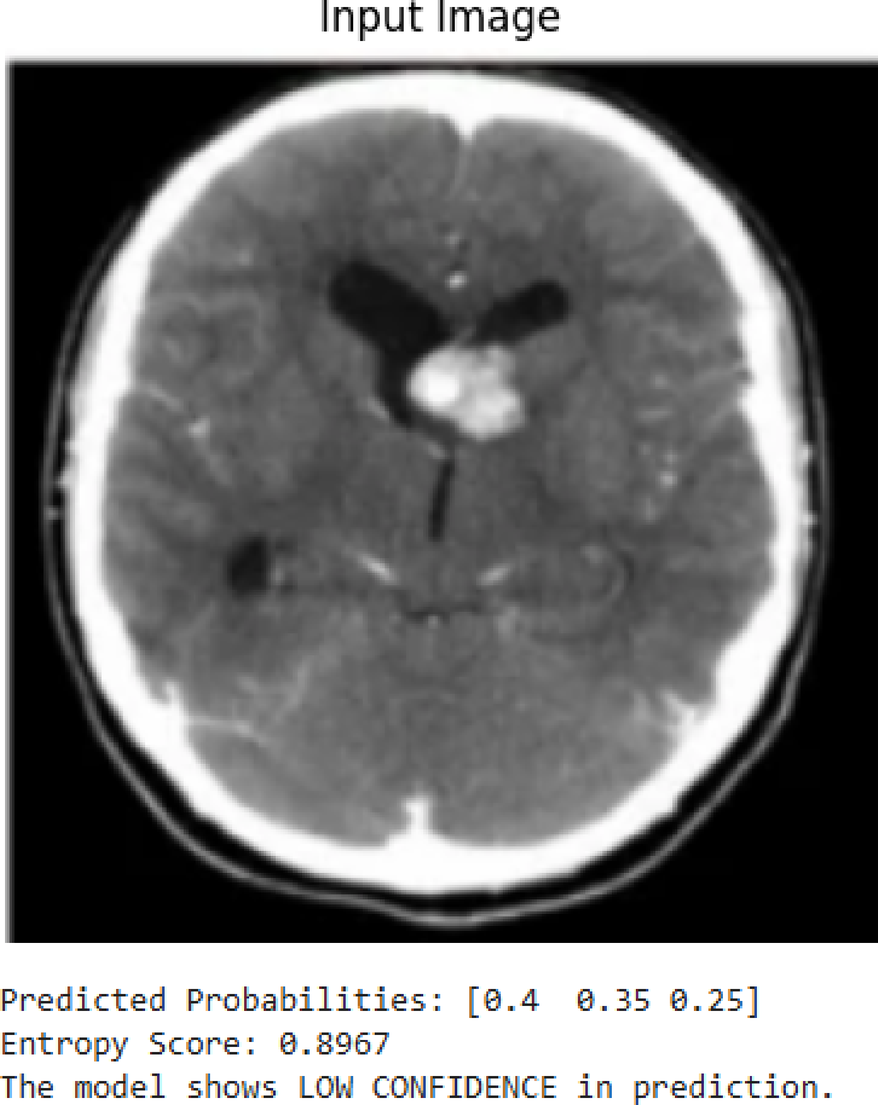

Fig. 23

Examples of low-confidence prediction.